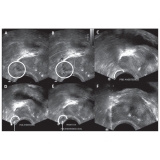

Procurando por biopsia de próstata? A urologia é uma especialidade da medicina que trata problemas do sistema urinário masculino e feminino, tratando também do sistema reprodutor masculino. Através da biópsia de próstata o médico Urologista pode obter amostras do tecido prostático, com o objetivo de identificar células cancerígenas. Para manter a saúde em dia é imprescindível realizar consultas periódicas ao médico para que seja feita uma avaliação.